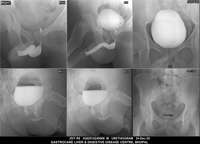

Section: URETHROGRAM

Total: 95 Cases

All Categories BaM Enteroclysis Loopogram BaE Fistulogram Urethrogram HSG